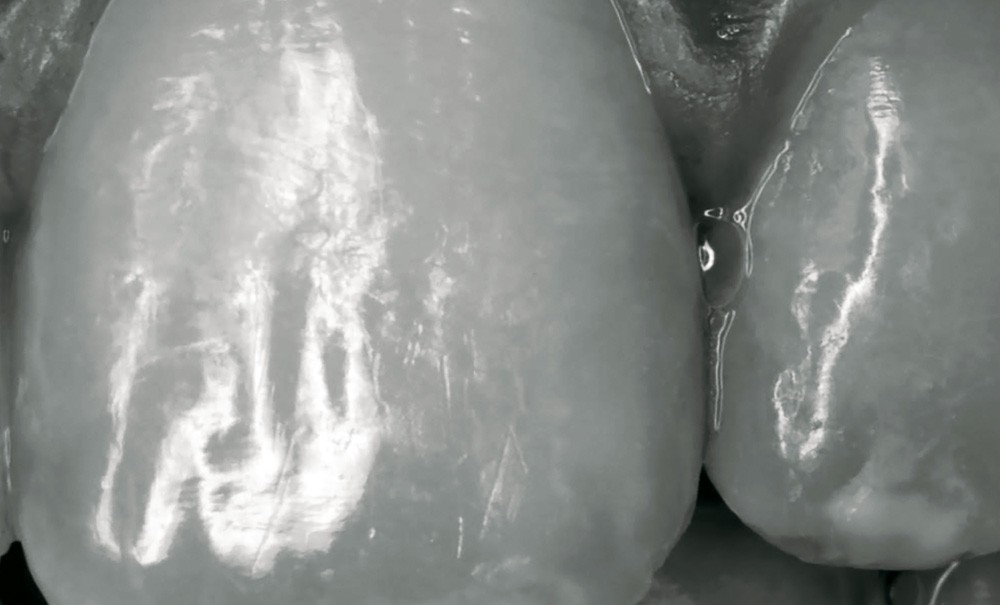

Il existe actuellement plus de 200 résines composites commercialisées pour les restaurations en technique directe. Bien que possédant les mêmes caractéristiques de base, elles n’en demeurent pas moins différentes et n’ont pas toutes les mêmes propriétés. Elles peuvent cependant être regroupées en fonction de certaines de leurs particularités. Cet article a pour but de présenter la classification des résines composites prenant en compte la diversité et les particularités de ces matériaux.

Parmi les différentes parties qui composent le matériau [1] (matrice organique, charges, agent de couplage organo-minéral), ce sont surtout les charges (nature, forme, taille, distribution, pourcentage) qui ont évolué dans les différentes formulations développées depuis les années 60. Ce sont elles qui influencent majoritairement les propriétés mécaniques et physiques et, de là, les indications cliniques du matériau. Par conséquent, ce sont les charges qui permettent habituellement de classer les résines composites (RC). Les autres particularités (polymérisation – photo, chémo, dual ; viscosité – standard, fluide, compactable) permettent d’en préciser la mise en œuvre et les indications cliniques.